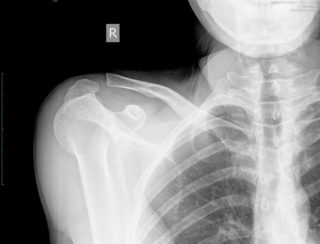

Переломы ключицы

Симптомы перелома сложно спутать с чем-то другим, ведь появляются они преимущественно после травм, о которых пациент помнит: удары, толчки, падения на выпрямленные руки или локти. Боль при переломах очень сильная, отечная, появляются синяки, кость может сменить привычное положение.

Вывихи и смещения

Вывих плечевого конца ключицы сопровождается острой болью

Грудинный конец ключицы, которым она крепится к клетке, может произойти из-за травм и падений, а также после ударов. Встречается патология редко и сопровождается такими симптомами:

- сильным отеком;

- выпячиванием ключицы или западанием;

- болью и покраснением.

Другой конец, акромиальный, имеет несколько связок, которыми крепится к лопаткам. Если они рвутся, пациент испытывает острую боль, возможность повернуть плечом резко ограничивается.